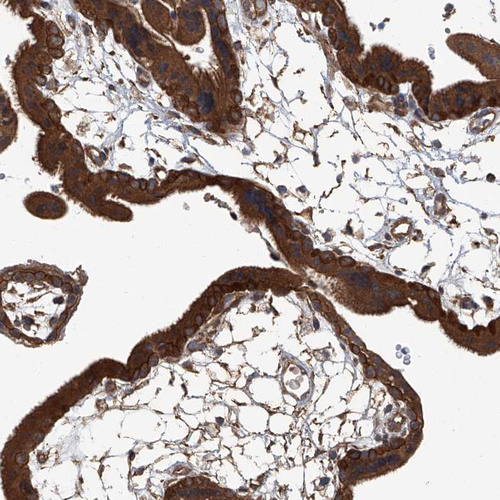

Immunohistochemical staining of human placenta shows strong cytoplasmic positivity in trophoblastic cells.